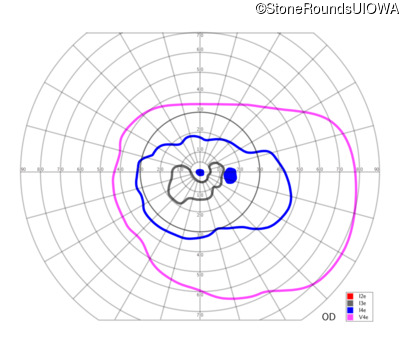

Congenital Stationary Synaptic Dysfunction (IA2g)

Congenital Stationary Synaptic Dysfunction (IA2g)

| Congenital Stationary Synaptic Dysfunction | CABP4 | Arg49Stop CGA>TGA | IVS1+1 G>T | AR |